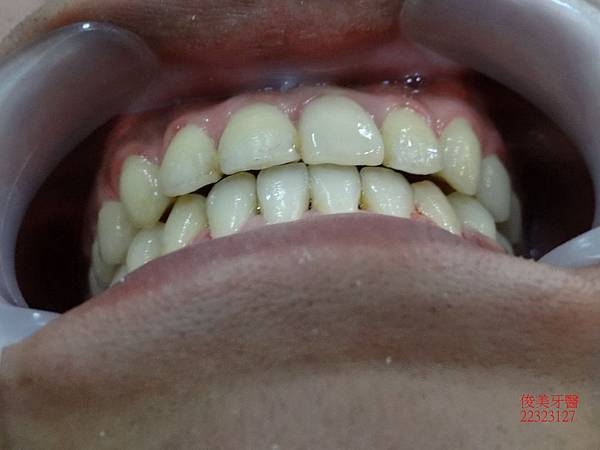

做完超自然、完美,牙齦邊緣幾乎看不出來;全部療程在1年左右結束。

患者超級滿意。

目前配戴維持器,定期檢查即可 。